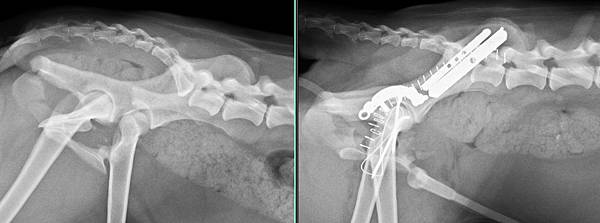

經過醫療團隊努力一一修復

虎妹妹很勇敢的恢復良好

未命名.jpg

手術後一周